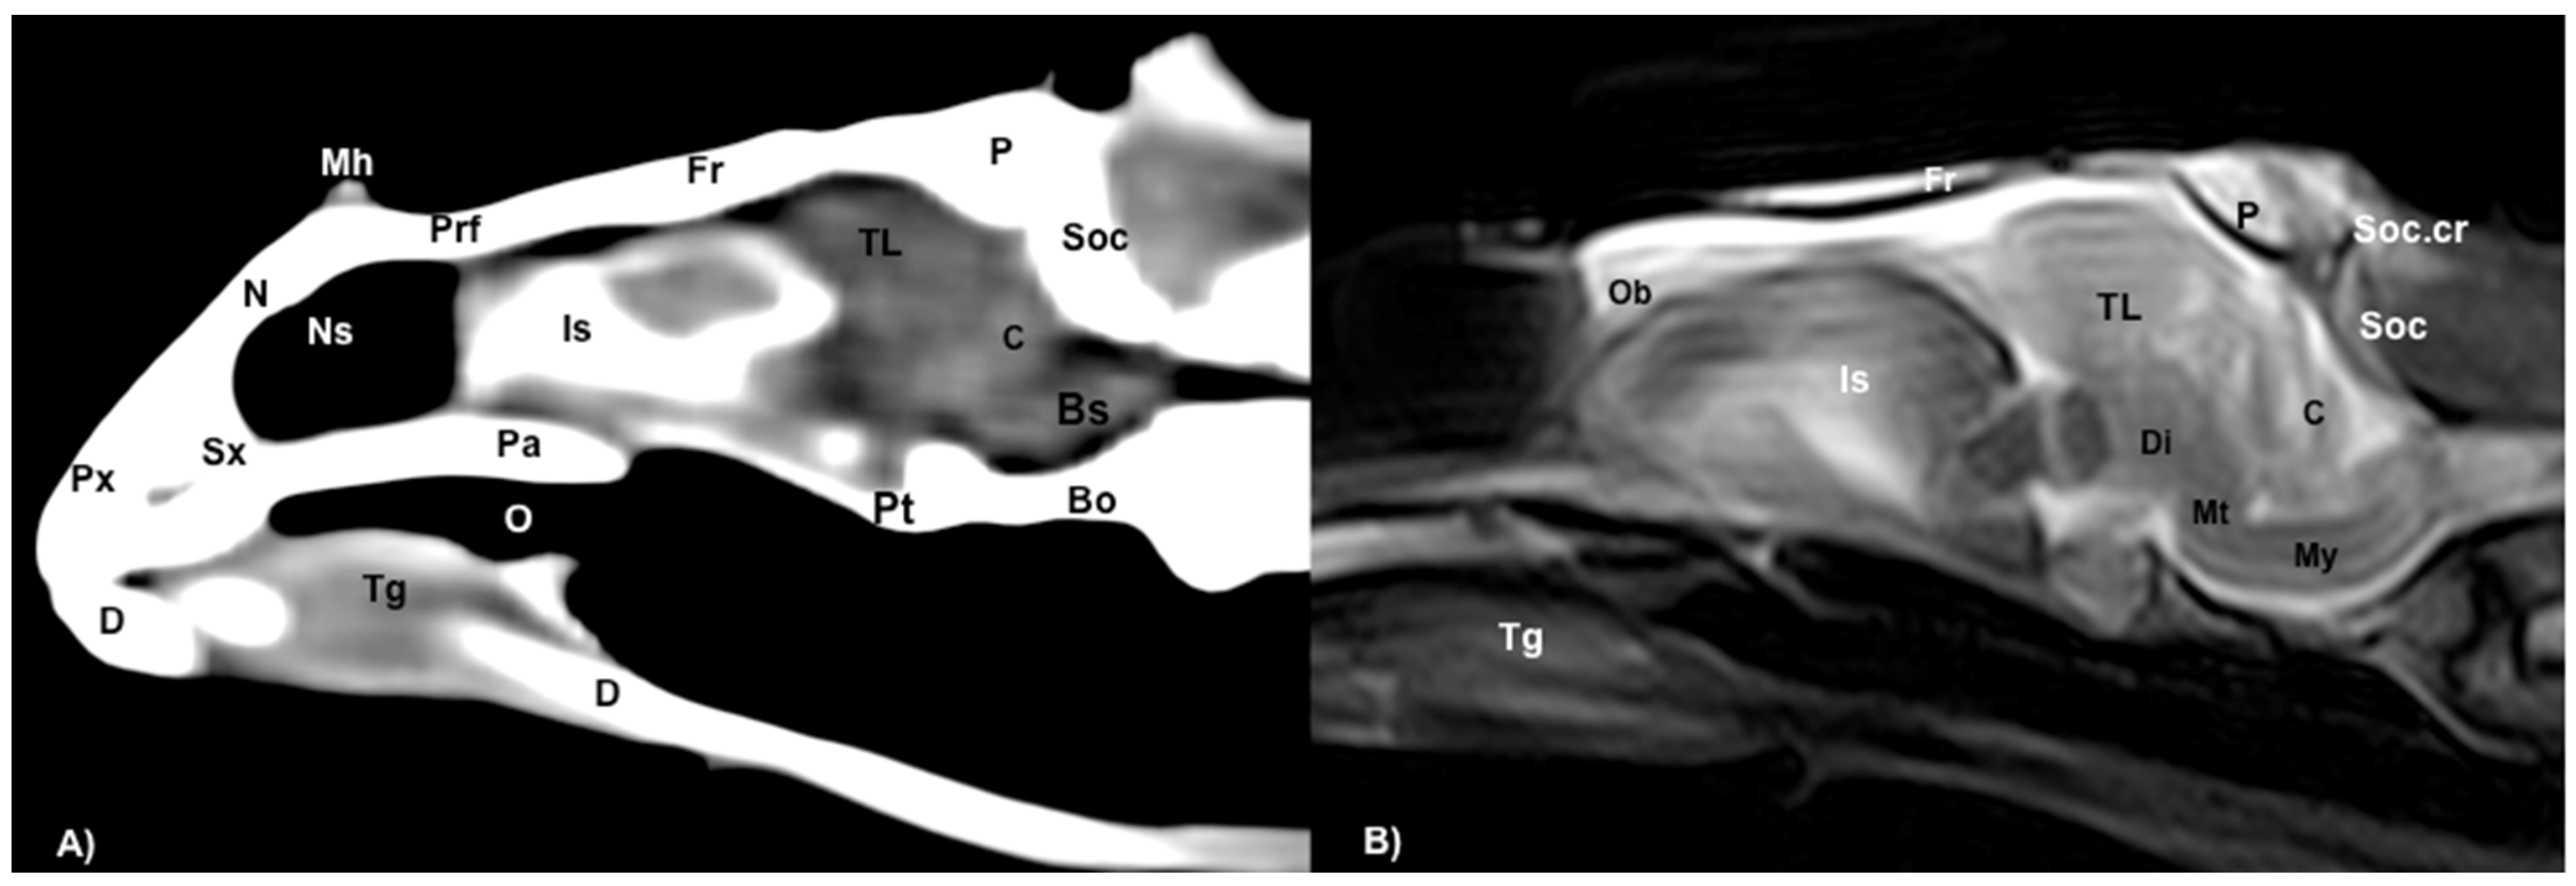

Figure 8.

(A) Mid-sagittal CT image in the brain window. (B) Sagittal MRI in the T2W sequence image of the head of rhinoceros iguana. Px: Premaxillary bone. Sx: Septomaxilla. D: Dentary bone. N: Nasal bone. Mh: Medial horn. Prf: Prefrontal bone. Pa: Palatine bone. O: Oral cavity. Tg: Tongue. Fr: Frontal bone. Is: Interorbital sinus. P: Parietal bone. Soc: Supraoccipital bone. Soc.cr: Supraoccipital crest. Pt: Pterygoid bone. Bo: Basioccipital bone. Ob: Olfactory bulbs. TL: Telencephalon. C: Cerebellum. Bs: Brainstem. Di: Diencephalon. Mt: Metencephalon. My: Myelencephalon.

Different structures belonging to the central nervous system were visualized by anatomical gross-sections. Therefore, we identified the brain (telencephalon) and the two telencephalic hemispheres (Figure 4A and Figure 5A) separated by the fissura longitudinalis cerebri (Figure 5A), the diencephalon (thalamus) (Figure 4A and Figure 5A), the dorsal part of the mesencephalon with the two caudal colliculus (Figure 6A) and the ventral part of the cerebellum with the nodule, covering part of the fourth ventricle, as well as the ventral surface of the brainstem (myelencephalon) (Figure 6A). These sections were also helpful for the observation of the olfactory bulb that showed an extracranial location, ventral to the frontal bones, and coursed between the two eyeballs (Figure 3). In addition, these sections allowed the description of structures of the eyeball, identifying the cornea, the sclera, the retina, the vitreous humor, the lens, as well as associated structures such as the interorbital septum and the orbital sinus (Figure 3A and Figure 4A). In addition, these transverse sections allowed the identification of structures belonging to the oral cavity such as the tongue (Figure 2A) and other structures such as the larynx, with the corniculate tubercles of the arytenoid cartilage, the thyroid cartilage, and the laryngeal ventricle (Figure 3A), as well as of different structures of the nasal cavity such as the nasal glands that filled almost the entire cavity, the conchal grooves and the stammteil located laterally to the nasal septum (Figure 2A). Adjacent structures such as the trachea and the nasopharynx were also well identified (Figure 4A, Figure 5A and Figure 6A). Furthermore, most bony structures that form the neurocranium were observed, such as the pterygoid, frontal, postfrontal-postorbital, parietal, supraoccipital, basioccipital, exoccipital, otoccipital, parabasisphenoid and sphenoid bones (Figure 3A, Figure 4A, Figure 5A and Figure 6A), as well as those that form the splanchnocranium such as the nasal, vomer, palatine and maxillary bones (Figure 2A and Figure 3A) and also the medial horn located dorsal to the nasal bone (Figure 2A), the mandible, with the dentary bone (Figure 3A), and the hyoid apparatus, visualizing the central body of the hyoid arch, between the lateral branches of the dentary bone (Figure 3A). Rostromedially to the two dentary bones, we identified different muscles related to the hyoid apparatus such as the musculus genihyioideus, hyoglossus and intermandibularis (Figure 2A and Figure 3A). In the following sections, we also observed the muscle groups corresponding to the mandibular musculature (we were not able to dissect them, and therefore they were treated as a group), including the pterygoideus, omohyoideus, sternohyoideus, ceratohyoideus, adductor mandibulae externus medialis and its homonym superficialis (Figure 4A and Figure 5A).

Regarding the neurocranium, the CT images allowed us to distinguish bone structures such as the prefrontal, frontal, postfrontal-postorbital, parietal, squamosal, quadrate, epipterygoid, pterygoid, basioccipital, exoccipital, otoccipital and parabasisphenoid bones (Figure 3B, Figure 4B, Figure 5B and Figure 6B); related to the splanchnocranium, we observed the nasal, premaxilla, maxilla, septomaxilla, vomer, jugal and palatine bones, and the nasal septum (Figure 2B, Figure 3B, Figure 4B, Figure 7B and Figure 8B); the mandible structures such as the dentary, angular, surangular, coronoid and articular bones (Figure 2B, Figure 3B, Figure 4B, Figure 5B and Figure 6B) and the hyoid apparatus (Figure 2B, Figure 3B, Figure 4B, Figure 5B and Figure 6B). CT scanning and post-processing transverse images showed the relation between the different bones that form the head of the rhinoceros iguana, the junction of the nasal and the prefrontal bone, as well as that of the parietal bone with the postfrontal-postorbital bone (Figure 2B and Figure 4B), and the palatine and quadrate processes of pterygoid bone (Figure 5B and Figure 6B respectively). The prominent medial horn was identified dorsal to the nasal bone with soft-tissue attenuation and a thin, lamellar-shaped mineral structure bordering it regularly on its most external aspect (Figure 2B).

Concerning the nasal cavity, the transverse CT image showed the nasal glands as symmetrical bilateral structures, with regular and well-defined margins, located on both sides of the nasal cavity and with soft tissue attenuation (Figure 2B). Moreover, those structures with intraluminal gas content such as the nasal conchal recess (Figure 2B), oral cavity, nasopharyngeal duct, trachea, adductor fossa (Figure 4B) and the otic cavity (Figure 6B) were identified with this technique, appearing with a vacuum effect. In addition, there were areas of soft tissue attenuation medial to the mandible and bilateral to the hyoid apparatus, compatible with the intermandibularis, genihyioideus and hyoglossus muscles (1 in Figure 2B and Figure 3B), the pterygoideus, omohyoideus, sternohyoideus and ceratohyoideus muscles (2 in Figure 4B), the adductor mandibulae externus medialis and superficialis muscles located, respectively, dorsomedially and ventrolaterally to the adductor fossa (3 and 4 in Figure 4B and Figure 5B).

3.3. Magnetic Resonance Imaging (MRI)

The soft structures of the iguana’s head, such as the central nervous system as well as the eyeball’s structures (vitreous humor and lens), the oral cavity with the tongue and the masticatory muscles, showed an accurate visualization using MRI (Figure 2C, Figure 3C, Figure 4C, Figure 5C and Figure 6C). Therefore, an increased volume of both eyeballs in proportion to the size of the head was seen in all sequences (Figure 3C and Figure 7B). As in CT, the structures with gas content (Figure 2C and Figure 6C) appeared with a vacuum effect, being hypointense in all sequences. The nasal glands were bilaterally symmetric, with regular and well-defined margins, located on both sides of the nasal cavity, being iso/hyperintense in T1W and T2W sequences, compared to the encephalic grey matter (Figure 2C and Figure 4C). In contrast, the medial horn appeared hypo/isointense on T1W and T2W sequences concerning the white matter and with mild differentiation of the external bony cortex in relation to the white matter (Figure 2C).

In contrast to the CT images, the bone junctions were not distinguishable on MRI, but those bones that formed the neurocranium, such as the frontal, postfrontal-postorbitary, parietal and supraoccipital bones were identified (Figure 3C, Figure 4C, Figure 5C, Figure 6C and Figure 8B). The cranial musculature was found isointense concerning the thalamus in T2W. This technique enabled a better resolution to identify the muscle groups already mentioned (Figure 2C, Figure 3C, Figure 4C and Figure 5C). In the transverse planes of the encephalon, the cerebral cortex was observed slightly more hyperintense than the white matter, which was more hypointense in T2W sequences (Figure 4C). The diencephalic region (Figure 4C, Figure 5C and Figure 8B) was hypointense (T2W) compared to the cerebral cortex (Figure 5C), showing the thalamus and hypothalamus (Figure 8B). The brainstem appeared hypo/isointense in T2W compared to the cerebral cortex, as well as presenting a markedly tortuous horizontal alignment (Figure 8B). Moreover, the caudal colliculus and the fourth ventricle were also displayed in excellent detail. In the rostral aspect of the telencephalon, we distinguished the dorsal pallium rostral part with its lateral and medial portions (Figure 4C). Interestingly, the dorsal MRI image was quite helpful to identify the olfactory bulb located extracranially, which extended rostromedially between the eyeballs (Figure 3C, Figure 7B and Figure 8B).

The use of MRI was valuable for visualizing organs located in the head. Thus, transverse MR images T2W facilitated the accurate identification of the main components of the brain, such as the telencephalon, diencephalon, mesencephalon, metencephalon and myelencephalon. Therefore, we identified specific structures such as the lateral ventricles, the anterior dorsal and posterior dorsal ventricular ridges, the cerebellum, the fourth ventricle, the dorsal pallium and the brain stem with the caudal colliculus. Interestingly, the dorsal MR T2W image showed the olfactory bulb isointense compared to the telencephalon, located in the rostral portion of the encephalon but in an extracranial situation, remaining in the rostromedial aspect of the eyeballs (extracranial structures). In contrast to other articles that excluded the olfactory bulb description, we present the shape, location and intensity of this structure [31]. This extracranial location was already observed in previous studies on the tawny dragon [31]. However, this finding had not been reported in other species of reptiles, such as the rhinoceros iguana. The gross-section images confirmed the presence of these structures and their rostral extension. Interestingly, in other species, such as galliform birds, the olfactory bulbs are separated from the telencephalic hemispheres but located intracranially, protected by the frontal bone [32].

In addition, the MRI and CT findings showed a greater angulation concerning the horizontal axis of the encephalon, with an angulation of 40° between the central horizontal axis of the skull and the central axis of the encephalon (dorsal displacement concerning the encephalon of the dog) (Figure 9), differing from other studies where an angulation of 28° was described [31]. In galliform birds, the brain has a similar angulation to the skull axis [32]. More similar aspects to the latter were found, such as the large size of the eyeballs, which were almost as large as the whole encephalon [32]. Nonetheless, further studies with a large number of animals should be performed to confirm these findings.